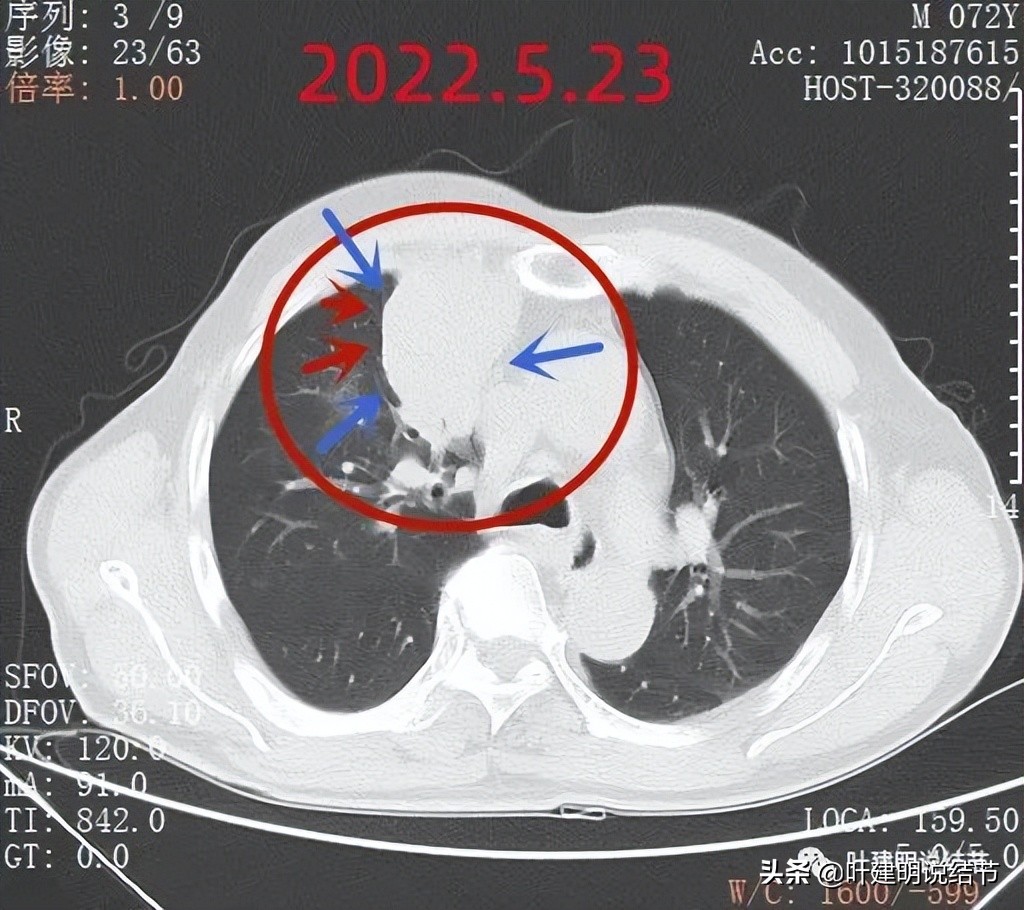

因为肿块巨大,整体看有些层面还是有鼓鼓的感觉的(红色箭头),但仍边缘过于光滑(蓝色箭头)

支气管似乎没有明显被侵犯或压迫(黄色箭头),边缘平滑(蓝色箭头)

到此,相关检查都没有肺癌的依据。我们在抗炎治疗约9天后予以复查胸部CT平扫,看病灶有没有变化。本来是考虑如果没有缩小好转,也先间隔4-6周再复查下再决定是否重新活检或手术切除。不想短短几天,居然病灶有了明显缩小:

前后10来天,居然效果惊人的好!那肯定要考虑非肿瘤性的了。